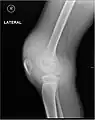

L'hémarthrose est un épanchement de sang dans une cavité articulaire consécutif d'une lésion ligamentaire, d'une fracture osseuse ou encore d'une atteinte du cartilage osseux[1]. Cette physiopathologie est caractéristique des personnes atteintes d'hémophilie sévère et dans une moindre mesure chez les formes modérées, car chez les hémophiles, l’absence ou l’altération d’un des facteurs de la coagulation (VIII ou IX selon le type d’hémophilie) perturbe le processus de la coagulation, au point qu’un traumatisme minime peut provoquer un saignement prolongé[2]

Près d'un quart des lésions sévères des ligaments et des genoux capsulaires entraînant une hémarthrose sont associées à des lésions cartilagineuses pouvant mener à une arthrite dégénérative progressive.